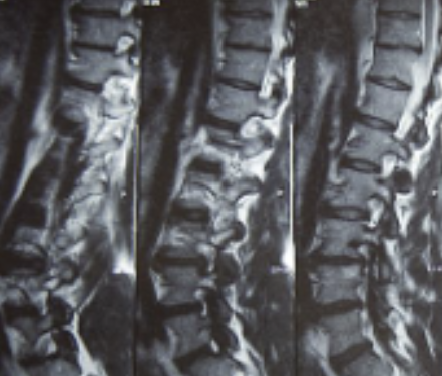

허리디스크를 정확하게 진단하기 위해서는 엑스레이로는 힘들며, MRI를 통해 검사해야 정확하게 볼 수 있습니다.

MRI가 몸에 좋지 않지만 허리 통증으로 엑스레이만 진행 할 경우 오진이 많아 지속적인 통증이 계속 된다면 허리디스크를 의심하고 MRI 검사를 한번 받아보시길 권유드립니다.

허리디스크는 디스크가 터져서 신경을 누를 경우 생기는 것으로 보통 4,5번에서 많이 발생하고 디스크가 터진 양이 적다면 터진 순간부터 수분이 날아가면서 양이 많이 없어지는데 그렇지 않고 양이 많을 경우 극심한 통증이 생깁니다.